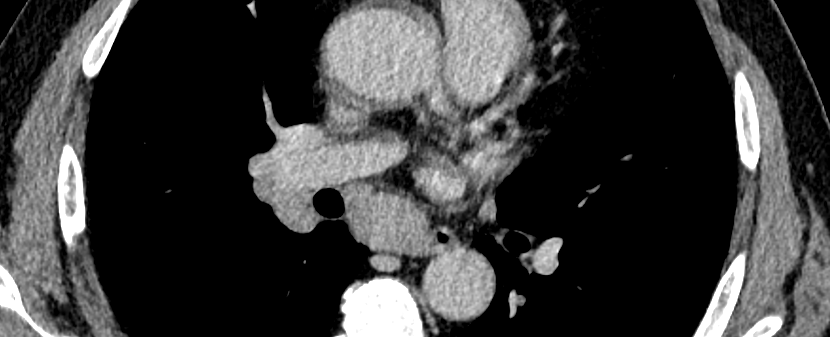

• Le syndrome de Löfgren se manifeste par la triade polyarthrite aiguë, érythème noueux et adénopathie hilaire

e991c7dbc92cd0494e078f69c666afa4.png f8f11fe1984681d61e2baec6b8978f2a.png